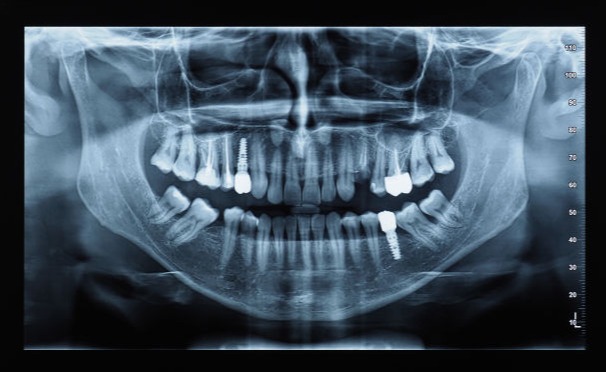

Tra i molteplici servizi dello Studio Domusdent rientrano anche le Panoramiche dentali o Ortopanoramiche, eseguite con strumentazioni avanzate che permettono l'acquisizione di immagini estremamente precise e comode grazie alla tecnologia 3D.

Assolutamente sì! Lo studio è provvisto delle più avanzate tecnologie odontoiatriche. Compreso il nostro Macchinario per l'esecuzione delle Panoramiche Dentali.